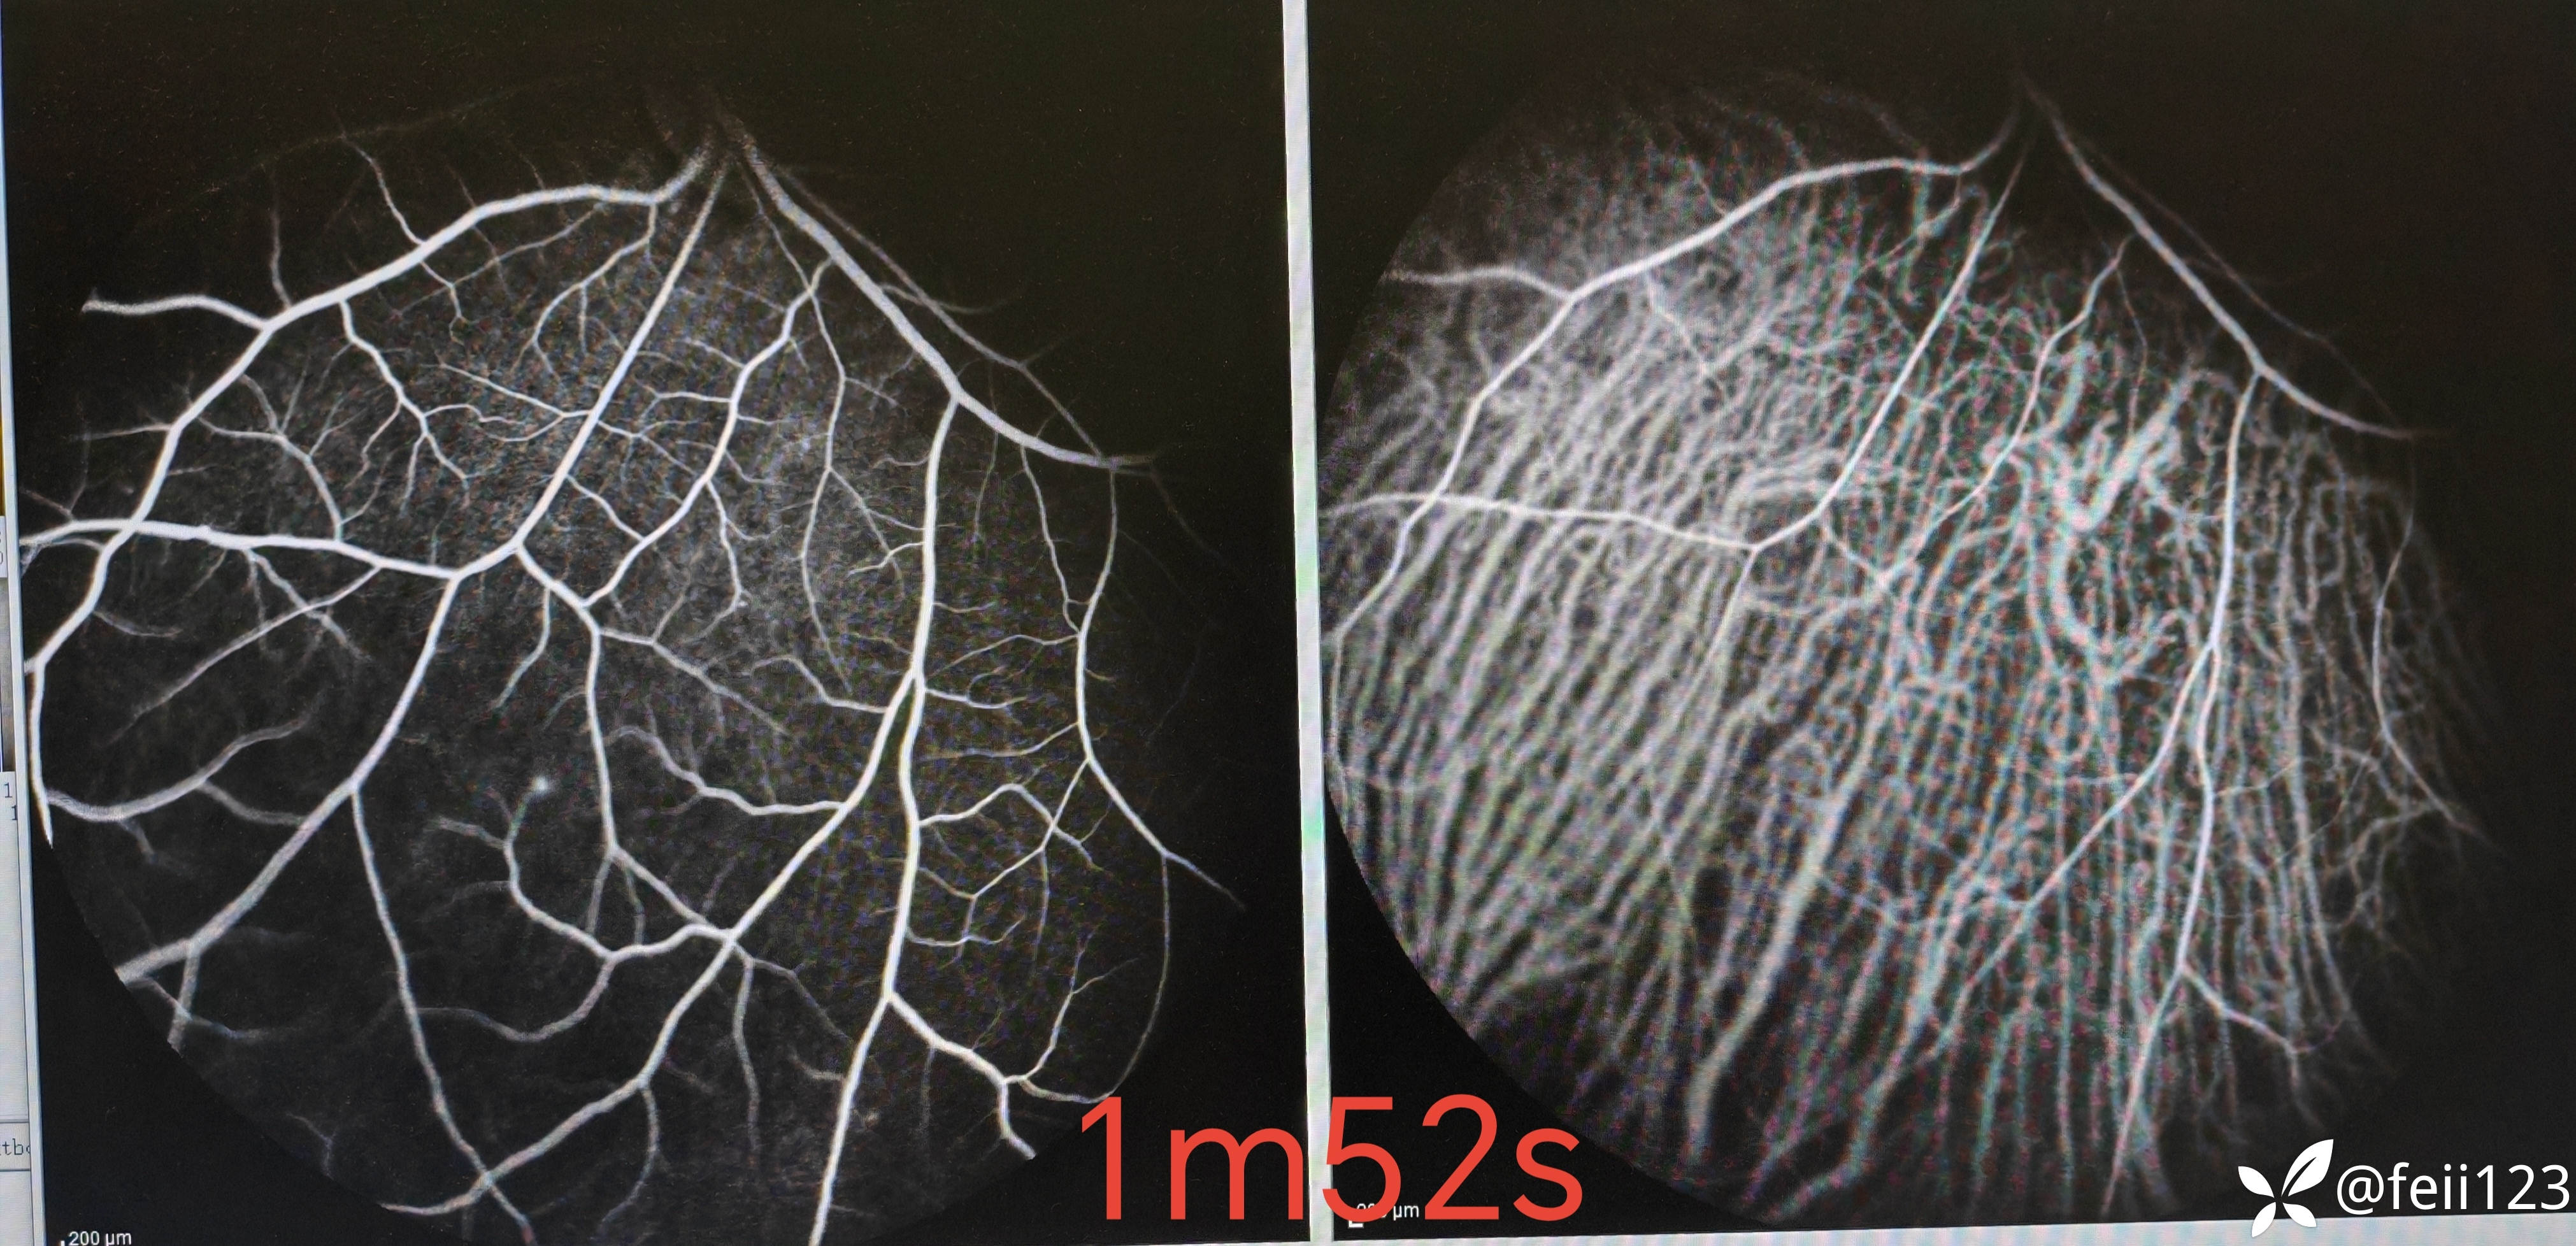

【检查】矫正视力右眼1.0左眼0.4,眼压正常15 16,眼前段未见异常,玻璃体清,眼底如图,左眼底可见后极部及鼻侧周边多个白点。

患者未完全确诊,想请教各位老师,这个患者的诊断,我考虑患者是白点综合症,但是AZOOR还是MEWDS还是其他比较有疑问,请大家指导